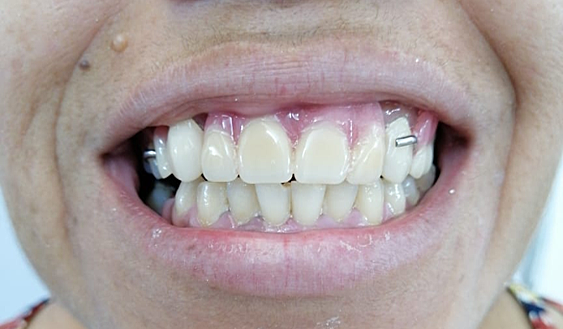

• FOTOS INTRAORALES

FOTOS INTRAORALES

Se realiza toma fotografica intraoral, donde se registra que el paciente se encuentra parcialmente edentulo tanto en carcada superior como inferior.

• ANALISIS DE SONRISA

ANALISIS DE SONRISA

La linea de la sonrisa no es valorable, esta linea se puede medir cuando hay organos dentarios anterosuperiores y anteroinferiores.